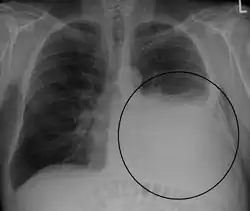

A pleural effusion appears as an area of whiteness on a standard posteroanterior chest X-ray.[15] Normally, the space between the visceral pleura and the parietal pleura cannot be seen. A pleural effusion infiltrates the space between these layers. Because the pleural effusion has a density similar to water, it can be seen on radiographs. Since the effusion has greater density than the rest of the lung, it gravitates towards the lower portions of the pleural cavity. The pleural effusion behaves according to basic fluid dynamics, conforming to the shape of pleural space, which is determined by the lung and chest wall. If the pleural space contains both air and fluid, then an air-fluid level that is horizontal will be present, instead of conforming to the lung space.[16] Chest radiographs in the lateral decubitus position (with the patient lying on the side of the pleural effusion) are more sensitive and can detect as little as 50 mL of fluid. Between 250 and 600mL of fluid must be present before upright chest X-rays can detect a pleural effusion (e.g., blunted costophrenic angles).[17]

Chest computed tomography is more accurate for diagnosis and may be obtained to better characterize the presence, size, and characteristics of a pleural effusion. Lung ultrasound, nearly as accurate as CT and more accurate than chest X-ray, is increasingly being used at the point of care to diagnose pleural effusions, with the advantage that it is a safe, dynamic, and repeatable imaging modality.[18] To increase diagnostic accuracy of detection of pleural effusion sonographically, markers such as boomerang and VIP signs can be utilized.[19]

-

Massive left-sided pleural effusion (whiteness) in a patient presenting with lung cancer. -